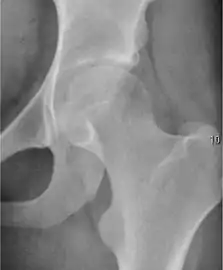

Synovial chondromatosis can be confidently diagnosed by X-ray when calcified cartilaginous chondromas are seen. However, other synovial proliferative processes, such as pigmented villonodular synovitis, require MRI for accurate diagnosis, although noncalcified synovitis can be suspected in radiographs by indirect signs, such as soft tissue swelling and/or erosions in the femoral head, femoral neck, or acetabulum (Figure 7).[1]

Figure 7:

Axial CT image of pigmented villonodular synovitis eroding the posterior cortex of the femoral neck.[1]

Sagittal T2* gradient echo image showing a posterior soft tissue mass with hypointense areas secondary to hemosiderin deposition.[1]

X-ray of synovial chondromatosis.[1]

CT of synovial chondromatosis.[1]

In synovial proliferative disorders, MRI demonstrates synovial hypertrophy. In the case of PVNS, characteristic foci of low signal intensity related to hemosiderin deposition are better seen on gradient echo T2* images (Figure 7). In the case of synovial osteochondromatosis, the synovial hypertrophy is accompanied by intermediate signal cartilaginous loose bodies and/or low signal calcified loose bodies.[1]